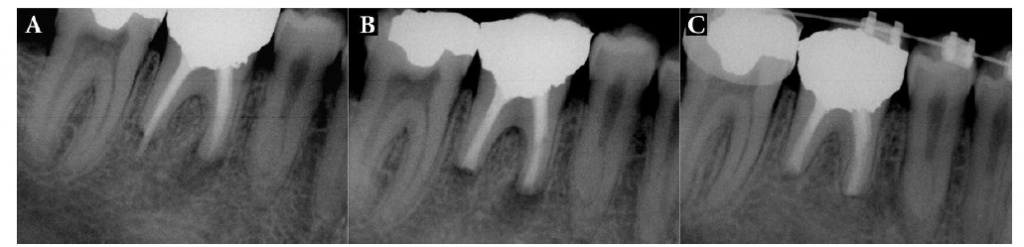

Рентгеновские снимки кариеса корня зуба

Раздел: Визуальные уроки